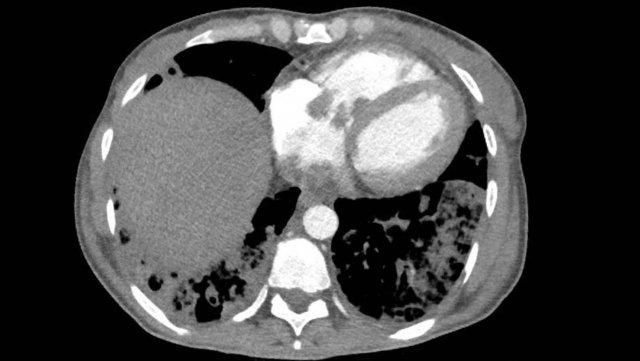

Hình ảnh

Nhĩ trái giãn.

Có huyết khối trong tiểu nhĩ trái (mũi tên) lan rộng về phía nhĩ trái (đầu mũi tên).

Tại tiểu nhĩ trái, thường gặp khó khăn trong chẩn đoán phân biệt hình ảnh giữa huyết khối và hiện tượng ngấm thuốc không hoàn toàn do dòng chảy chậm, đặc biệt khi chụp ở thì thuốc sớm.

Vấn đề này có thể được giải quyết bằng cách chụp CT ở thì thuốc muộn hơn hoặc chụp ở tư thế nằm sấp.

Siêu âm tim qua thực quản được coi là tiêu chuẩn vàng.

Xảo ảnh dòng chảy chậm trong tiểu nhĩ trái, với hình ảnh ngấm thuốc không hoàn toàn của tiểu nhĩ trái ở thì sớm nhưng lấp đầy hoàn toàn ở thì thuốc muộn hơn.